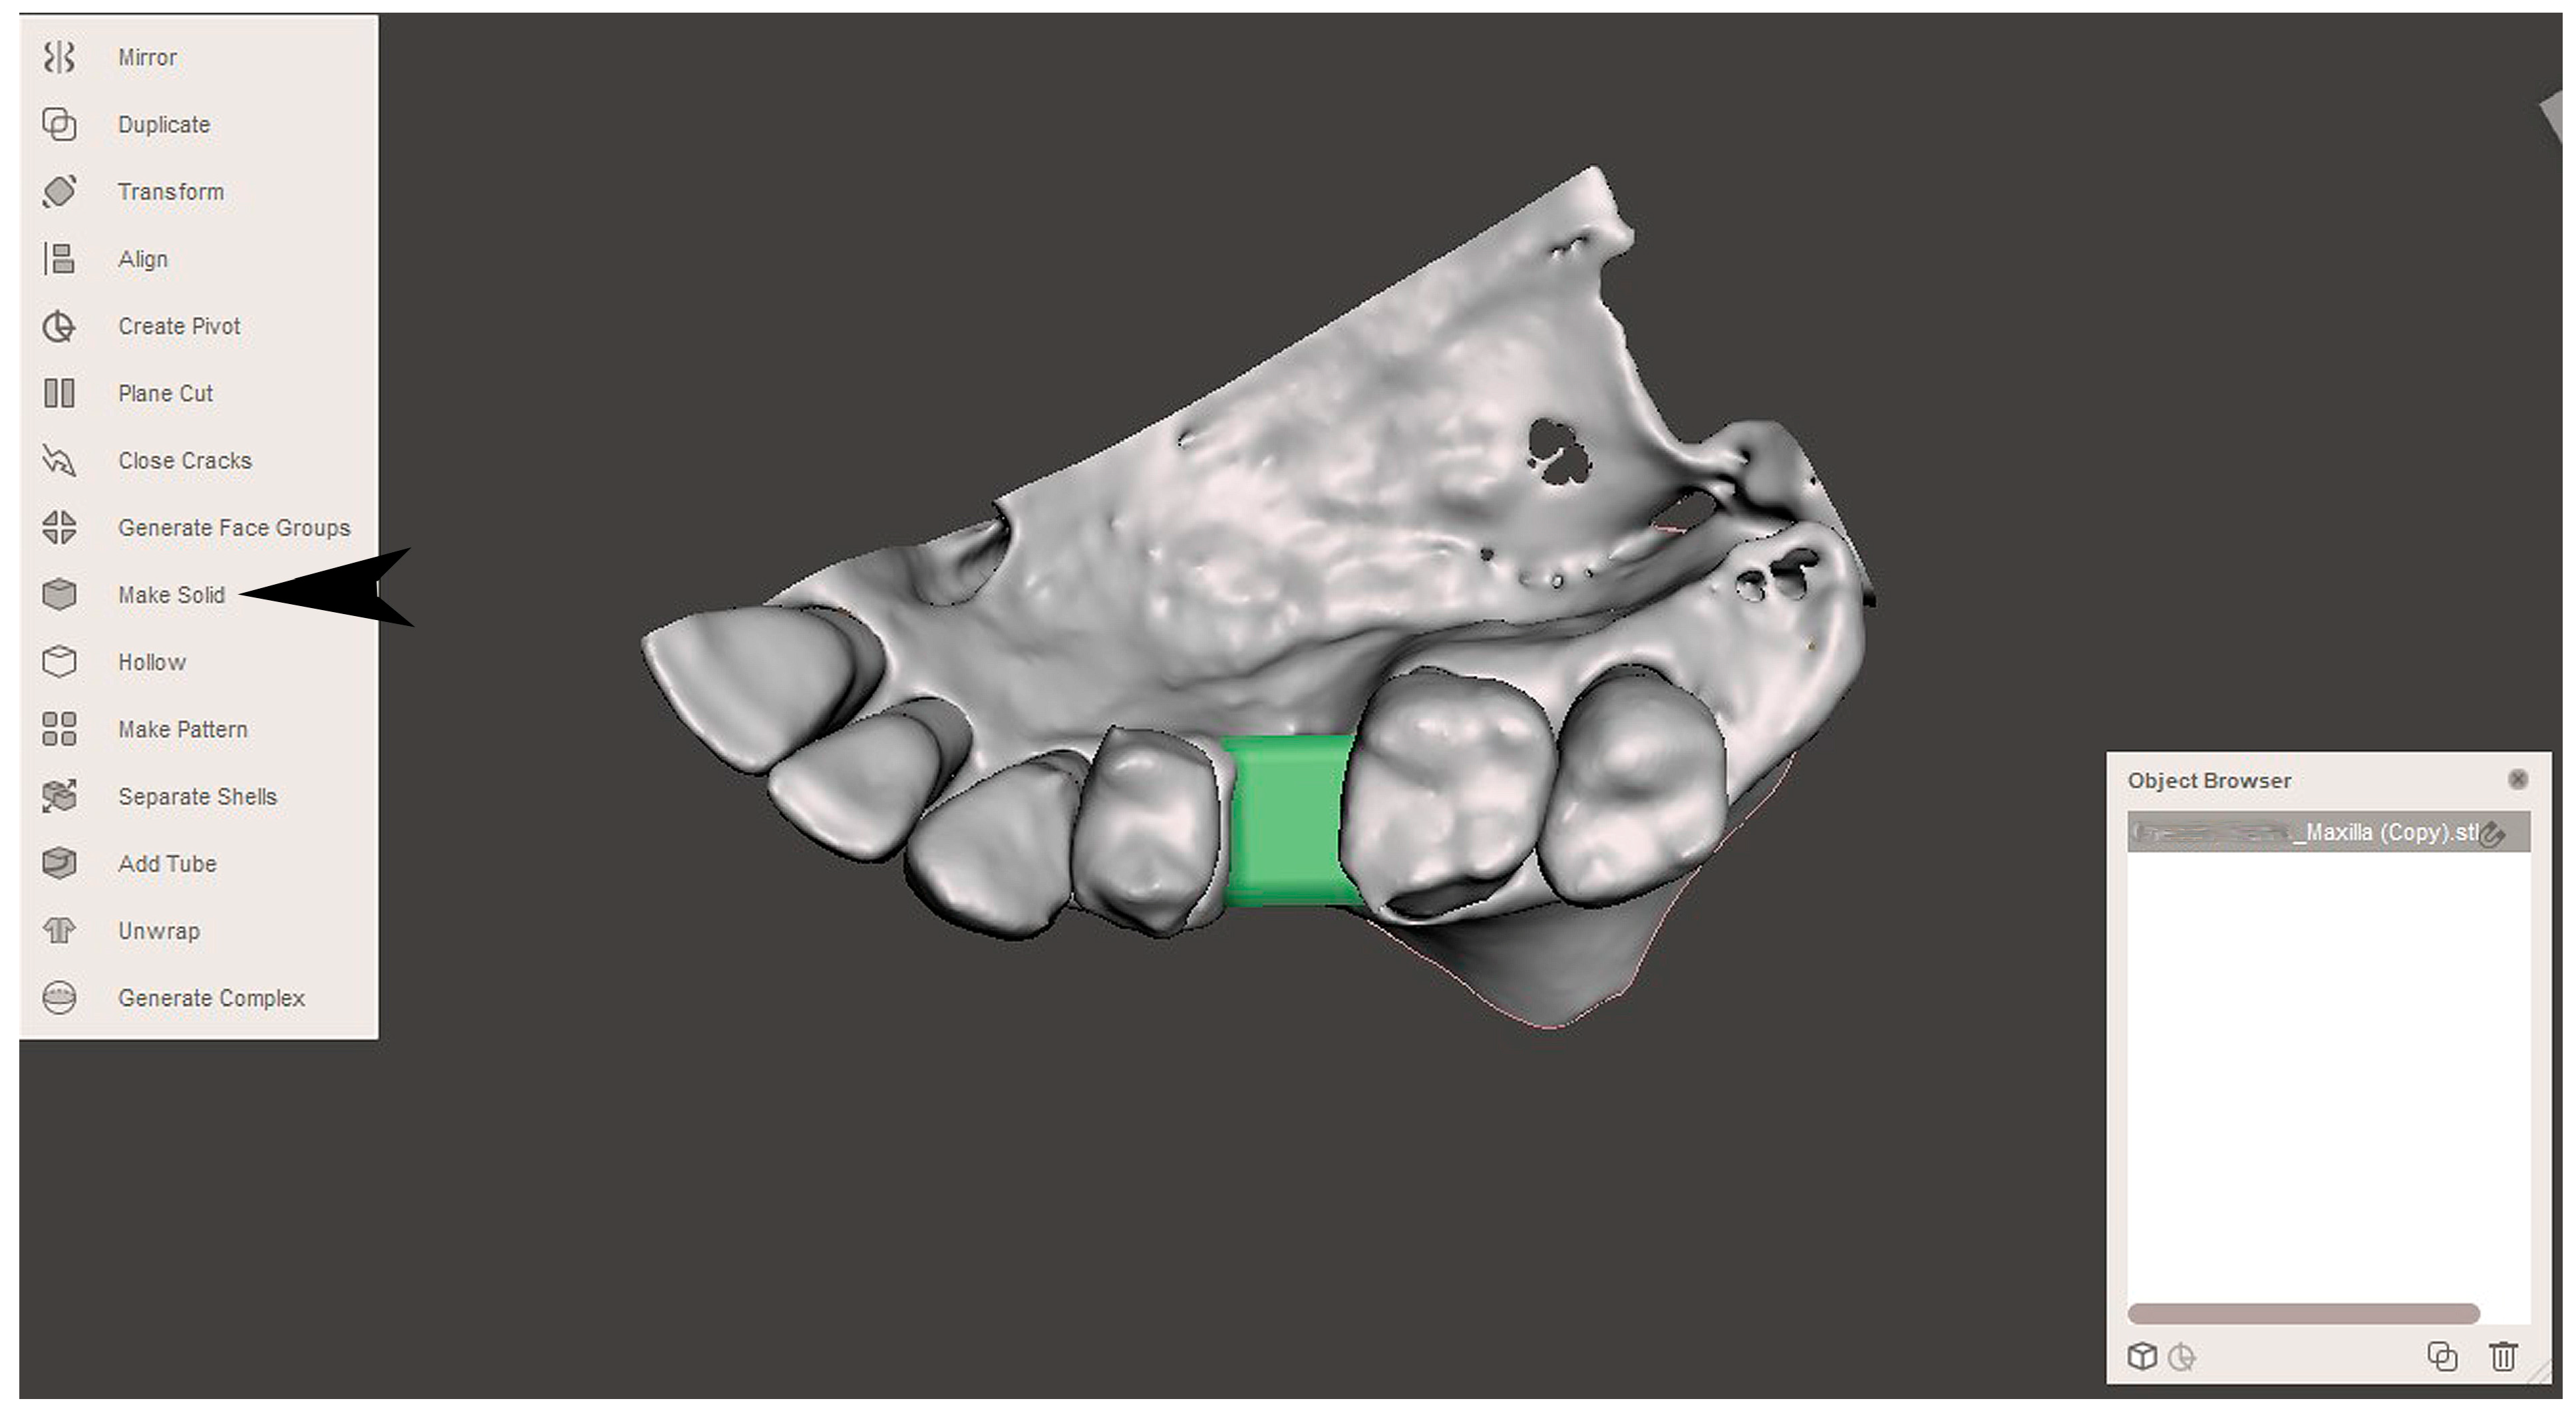

2.2. GBR Simulation and Mesh Design